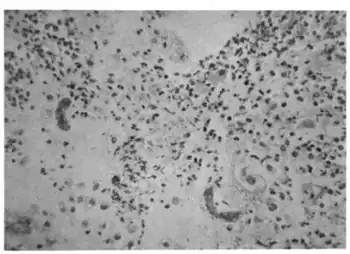

Hyperinfection with strongyloides stercoralis-Larvae in gastric mucosa[7]

As an antiparasitic, tiabendazole is able to control roundworms (such as those causing strongyloidiasis),[8] hookworms, and other helminth species which infect wild animals, livestock, and humans.[9]